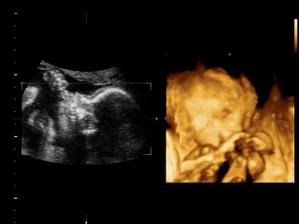

11.05. - (26+5) dnes jedeme na video

video se povedlo, máme asi 6 cca 5 - 10ti vteřinových videíí.Bylo to super. Karolínka se zase mlela jako drak. Je taková živoučká 😀

kontrola - vše v pořádku a máme + 8kg